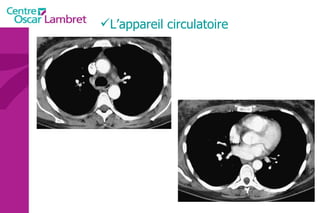

L’appareil circulatoire L’appareil circulatoire  s’appuie sur un véritable réseau aussi étendu que précis. Sous l’impulsion du  coeur , chef d’orchestre vital, les artères et les veines assurent le transport du sang indispensable à tout notre organisme.  Les artères  apportent le sang riche en oxygène et en nutriments à l’ensemble des tissus de l’organisme.  Les veines  doivent rapporter le sang appauvri en oxygène vers le coeur puis les poumons. Des  poumons , il repasse dans le coeur qui le propulse de nouveau via les artères à tout l’organisme.

Le cœur  se situe au milieu du thorax, sur le diaphragme, la pointe tournée vers la gauche. L’appareil circulatoire

L’appareil circulatoire Le coeur  est un organe formé essentiellement d'un muscle, le myocarde, lequel est entouré d'un "sac" séreux, le péricarde et tapissé à l’intérieur par une fine membrane, l'endocarde.

Le coeur  comprend quatre cavités :  deux cavités droites, formées par l’oreillette (ou atrium) et le ventricule droit.  deux cavités gauches, formées par l’oreillette (ou atrium) et le ventricule gauche.  Les cavités droite et gauche sont totalement séparées par une cloison (septum).  Ces cavités sont connectées à des veines et des artères qui conduisent le sang venant ou partant du coeur.  L’appareil circulatoire

Les 2  atriums  ont un petit diverticule : les auricules Le cœur repose sur le diaphragme et est situé au niveau de la partie antérieure et inférieure du médiastin. Le coeur est bordé latéralement par les poumons qui le recouvre partiellement. Les 4 cavités du coeur sont limitées par des sillons. Le  sillon coronaire le sillon inter atrial  Le sillon inter ventriculaire ou septum L’appareil circulatoire